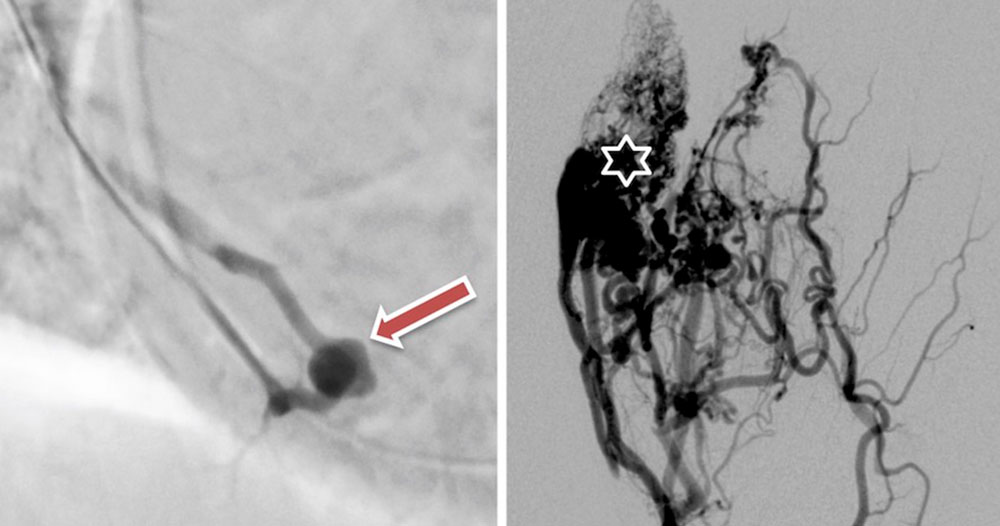

An arteriovenous fistula (AVF) is an abnormal, direct and simple connection between an artery and a vein as opposed to a typical AVM where the connections are multiple complex, net-like structures. In this condition, the capillary bed that normally connects arteries and veins is bypassed, creating a short-circuit connection (shunt). An arteriovenous fistula can be congenital or acquired, e.g., through trauma.

A congenital arteriovenous fistula is the simplest form of arteriovenous malformation (AVM) with a direct connection. Like all vascular malformations, congenital AVFs are not acquired. The vessels that form the short-circuit connections between the arterial and venous systems in an arteriovenous malformation can vary in number, diameter, length and configuration, and are collectively referred to as the nidus.